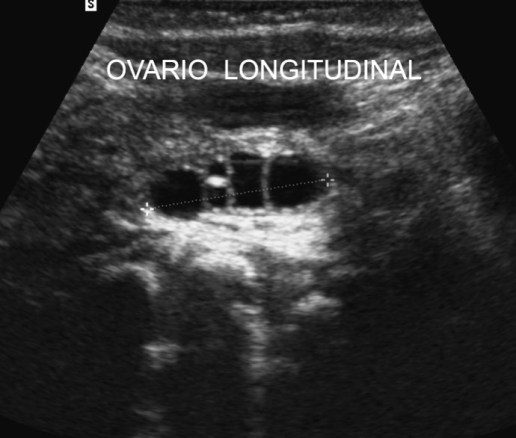

Ovario. Medidas.

Los ovarios tienen forma elíptica. Diámetro mayor de unos 3,5 cm y 1,5 cm. de espesor.